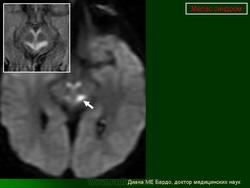

При первичном проведении МРТ головного мозга в левой затылочной доле обнаружена обширная зона гиперинтенсивного сигнала в режиме Т2 и гипоинтенсивность в режиме Т1 с четкими контурами, срединные структуры не смещены. Данная радиологическая картина была расценена как явление ишемического инсульта.

Наросла вялость, слабость, появилась приступообразная головная боль с однократной рвотой. Повторно проведена МРТ головного мозга — в режимах Т1 иТ2 визуализировались участки измененного сигнала в теменно-затылочных отделах с обеих сторон (причем очаг слева имел меньшие размеры по сравнению с таковым при предыдущем МРТ-исследовании). Таким образом, за прошедшие после первого инсульта несколько месяцев мальчик перенес по крайней мере еще три острых нарушения мозгового кровообращения.

МРТ головного мозга: гиподенсивный очаг в проекции теменной области справа — ОНМК по ишемическому типу. Энцефалопатия. Субатрофия головного мозга с признаками эктазии желудочков.